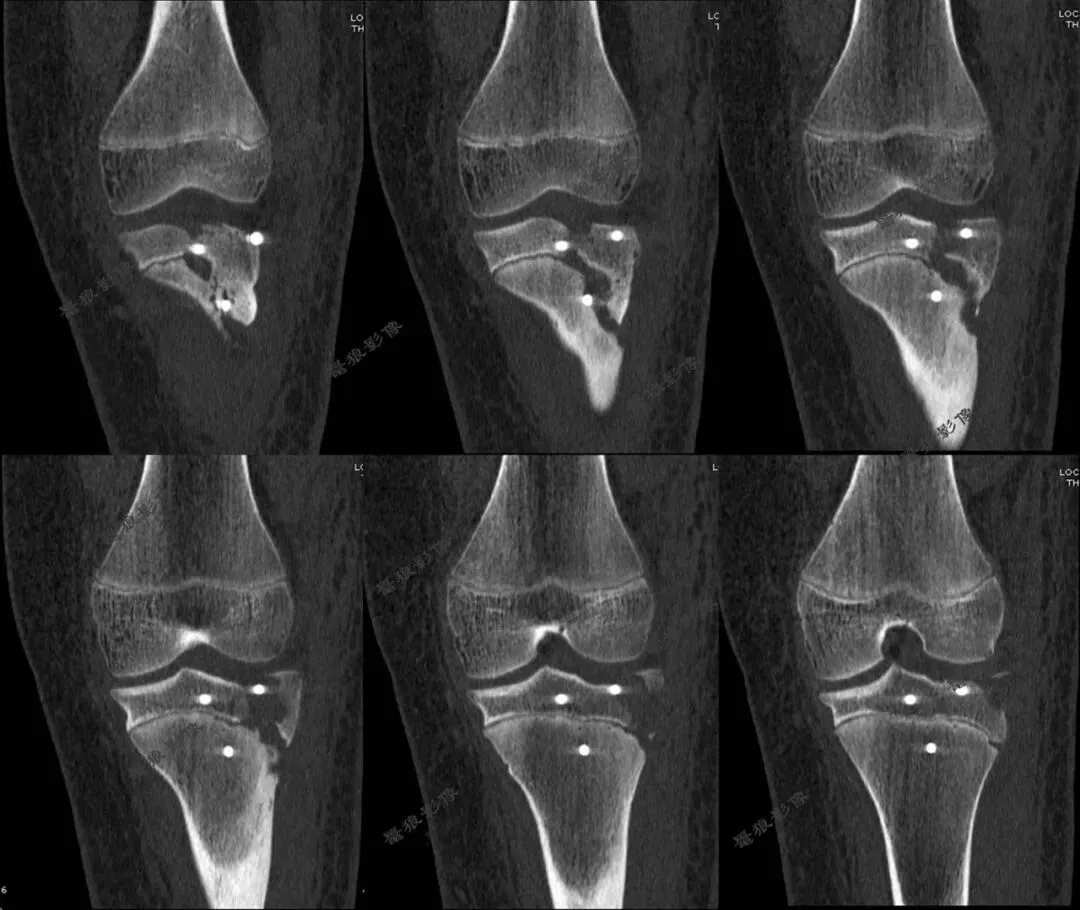

D、胫骨结节骨折病例分享

M,11y。

缘患者入院3小时余前运动后出现左膝部疼痛,活动受限,当时无昏迷,遂送至急诊就诊,查X片:左胫骨结节骺离骨折。

二.术前CT

胫骨结节骨折(OgdenIIIA型 )